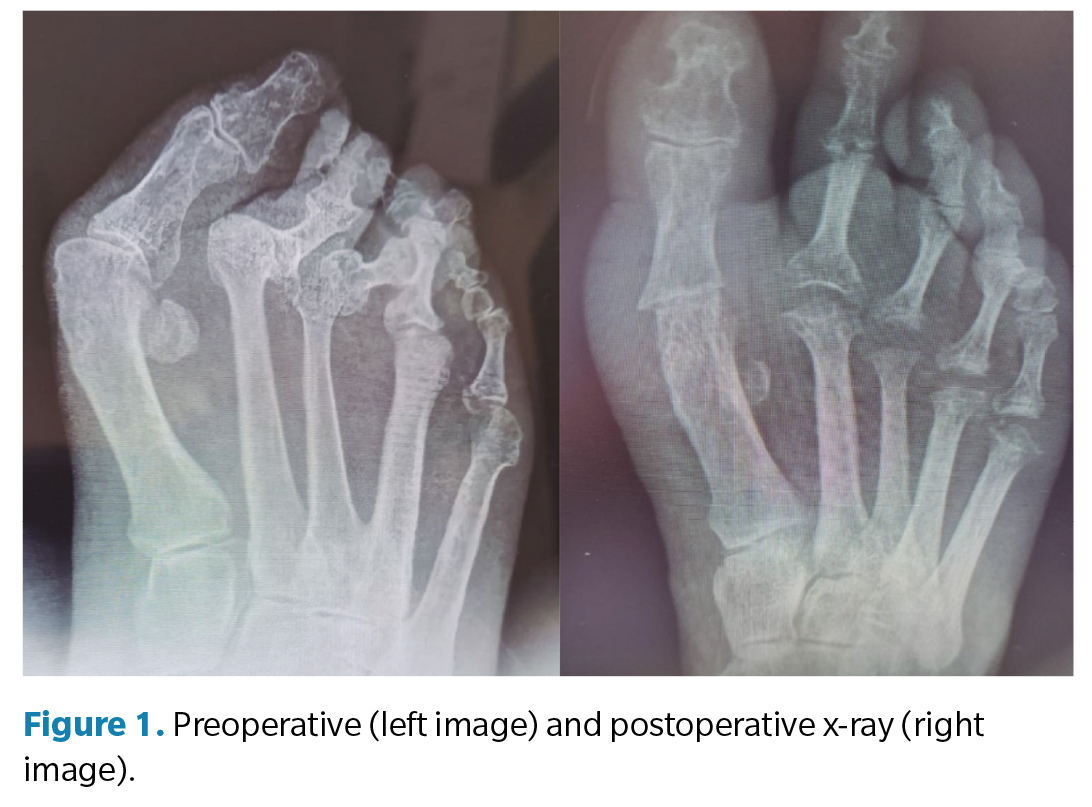

Prior to data collection, the medical history was reviewed to collect generic variables (height, weight, body mass index, and laterality), surgical risk categorization (ASA scale), deep vein thrombosis risk categorization (Autar scale), SF-36 scale, AOFAS scale, reason for consultation, and clinical assessment of pain (VAS scale). Preoperative assessment consisted of a clinical examination to observe the deformity, both in weight-bearing and non-weight-bearing, and various maneuvers were performed to assess joint ranges of motion, paying attention to the location of pain and/or different hyperkeratosis associated with the deformity. Additionally, a vascular study was conducted in which pedal and posterior tibial pulses were palpated accompanied by an echo-Doppler and ankle-brachial index (ABI) measurement. Furthermore, a gait biomechanical study, both baropodometric and dynamic, was performed, and finally, a radiological study (Figure 1) of the foot to be operated.

Along with these scales, a radiological analysis of the deformity on the Weight-Bearing Dorsoplantar X-ray was performed, assessing the following angles: intermetatarsal angle, hallux abductus valgus angle, Merchan angle, and hallux interphalangeal angle. This measurement was performed on preoperative x-rays and postoperative x-rays 1 year after surgery.

Regarding preoperative radiological angles, a mean of 18.3º was observed for the intermetatarsal I-II angle (IMA I-II) and 48.4º for the hallux abductus valgus angle (αHAV). After the intervention, the mean IMA I-II was 15º and the αHAV was 24.1º. Regarding the Merchan’s angle, mean preoperative and postoperative values of 141.7 and 141.6, respectively, were observed. In the case of the interphalangeal angle, mean preoperative and postoperative values of 5º and 3.3º, respectively, were seen (Table 3).